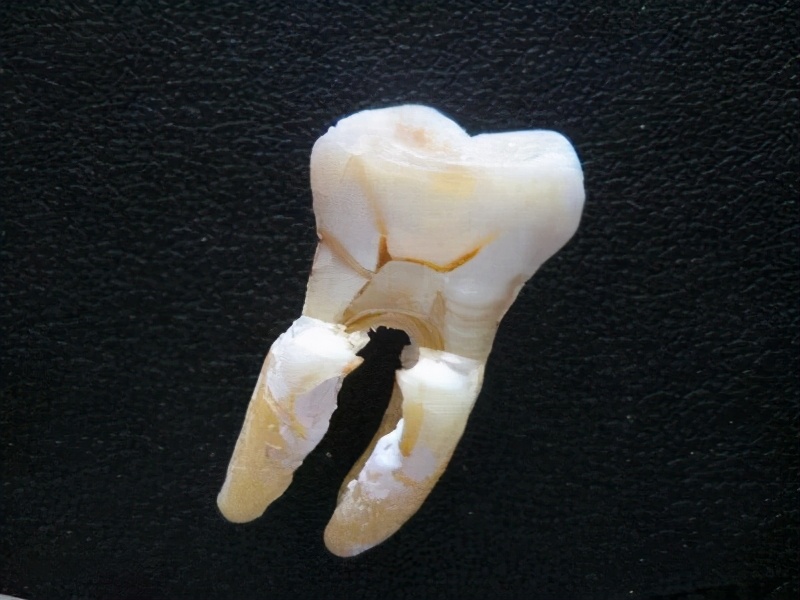

4、牙髓炎

牙髓炎的出现,多半是因为龋齿了没有去做填补,在洞口处残留大量的细菌,病毒入侵了牙齿细胞组织中,造成牙髓感染。当然还有另外一个原因就是,患者服用了刺激的药物,或者吃了什么食物诱发出来。牙髓炎引起的疼痛也很严重,如果真的忍不住就去医院治疗吧。